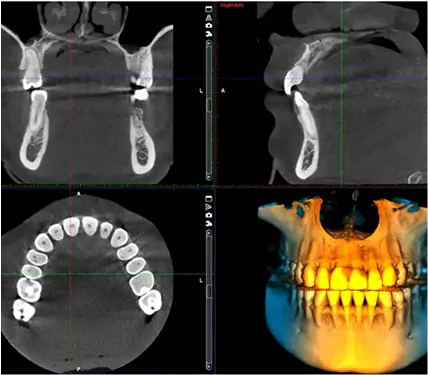

CBCT (Planmeca Pro 3D LEC)

Our imaging system also works comfortably with growing children. The system collects a panoramic 3D image around their entire head, removing the need to insert and bite down on a positioning tool that can often be too large and uncomfortable for a child’s mouth. We are proud to use this advanced imaging technology for improving patient outcomes and personalized care.